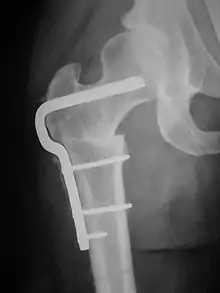

A subtrochanteric blade plate or an intramedullary rod can be used to stabilize the osteotomy site in a femoral derotation osteotomy until compete bone healing is achieved; an approach employing an intramedullary rod is much less invasive than one using a subtrochanteric blade plate.}